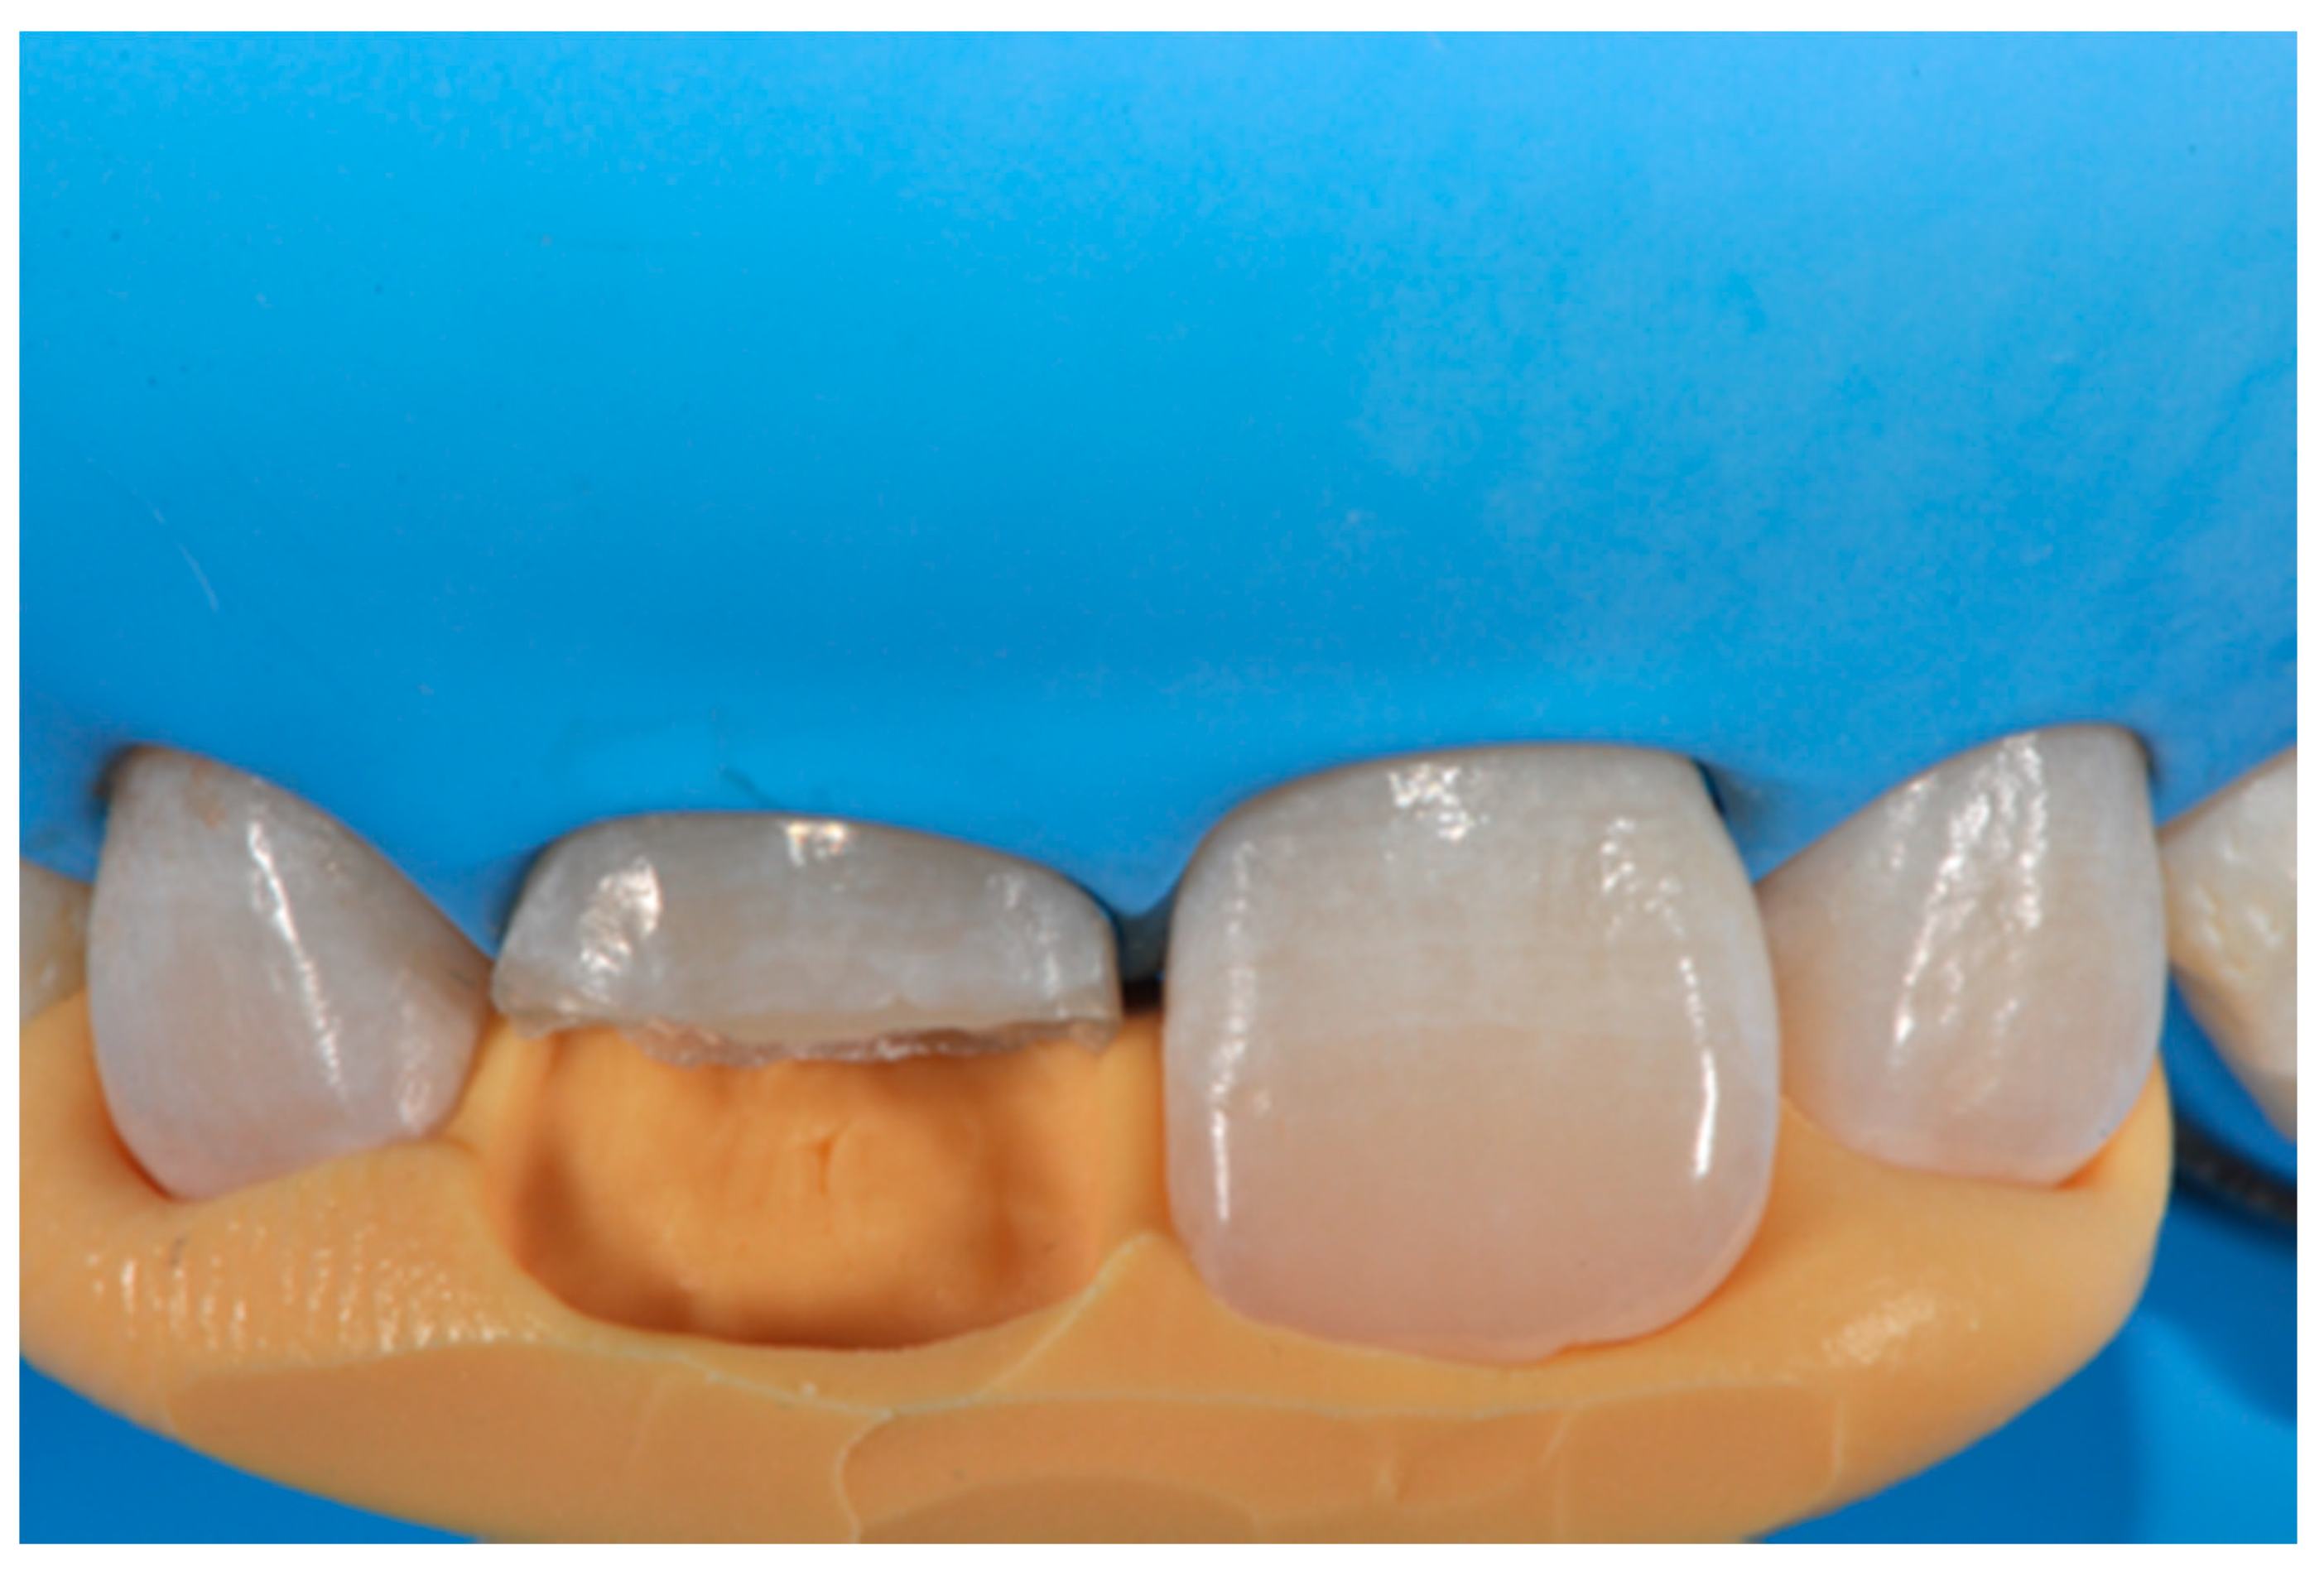

Figure 3.

Wax-up. Reprinted from Restauri diretti nei settori anteriori, G. Paolone, S. Scolavino, © 2021, with permission from Quintessence Publishing Italy.